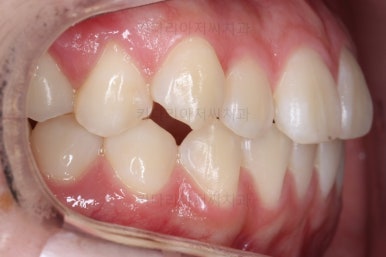

각각 왼쪽, 오른쪽의 교합의 모습입니다.

가장 좋은 교합은 위아래 치아들이 지그재그로 톱니바퀴 물리듯이 맞아들어가야 하는데 오른쪽 사진들 보면 중간중간 빈틈도 많이 보여요.

이런 교합은 장기적으로 치아 수명을 단축시킬 수 있습니다.